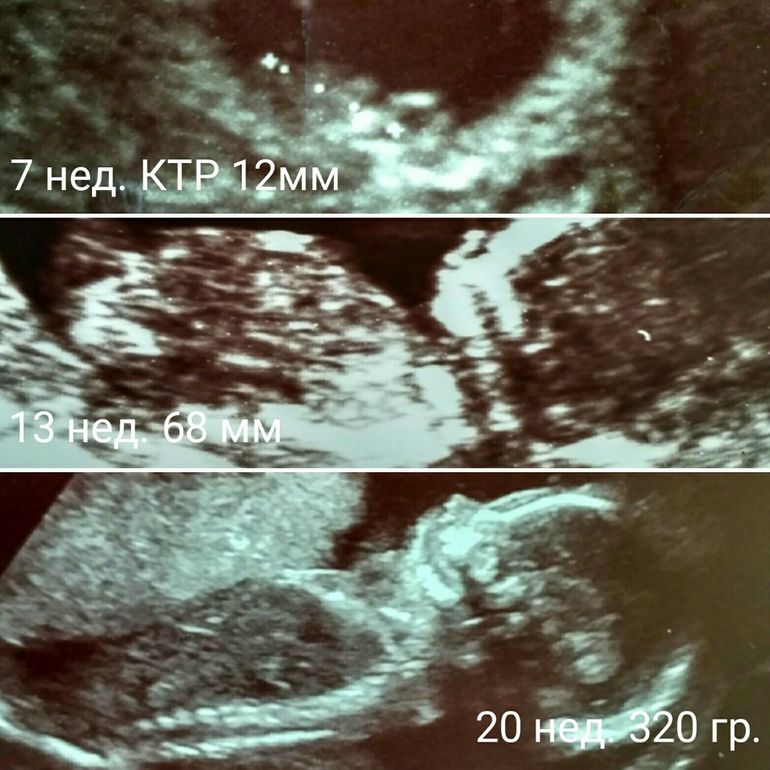

вот ее фотографии.